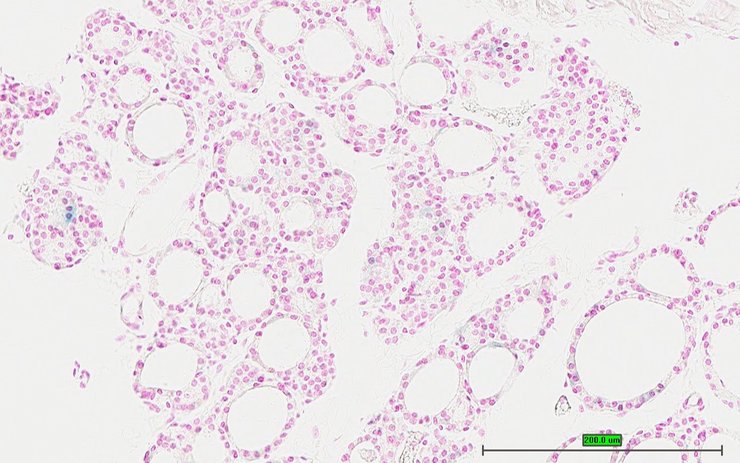

Specimen UC Davis_1880303: postnatal adult; Tlr2tm1.1(KOMP)Vlcg/Tlr2+ (more )

TS28: thyroid gland Present UC Davis_1880303

Specimen UC Davis_1880304: postnatal adult; Tlr2tm1.1(KOMP)Vlcg/Tlr2+ (more )

TS28: ileum Present UC Davis_1880304

Specimen UC Davis_1880305: postnatal adult; Tlr2tm1.1(KOMP)Vlcg/Tlr2+ (more )

TS28: colon Present UC Davis_1880305

Specimen UC Davis_1880306: postnatal adult; Tlr2tm1.1(KOMP)Vlcg/Tlr2+ (more )

TS28: metanephros Present UC Davis_1880306 kidney

Specimen UC Davis_1880301: postnatal adult; Tlr2tm1.1(KOMP)Vlcg/Tlr2+ (more )

TS28: ductus deferens Present UC Davis_1880301 vas deferens

Specimen UC Davis_1880302: postnatal adult; Tlr2tm1.1(KOMP)Vlcg/Tlr2+ (more )

TS28: ductus deferens Present UC Davis_1880302 vas deferens